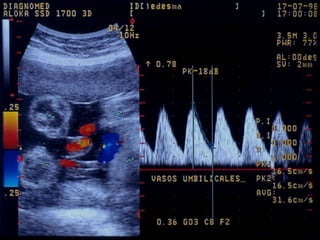

DOPPLER COLOR

Traducen las velocidades

medias del flujo en un vaso

sanguíneo

Es útil en casos de sospecha de

hipoxia crónica: RCIU,

hipertensión

El color refleja la dirección del

flujo sanguíneo respecto al

transductor

- Detecta presencia y

dirección del flujo en un

vaso

- Diferencia flujo laminar o

turbulento

- Valora grado de resistencia

que el flujo tiene que vencer

Arteria Umbilical NormalArteria Umbilical Normal